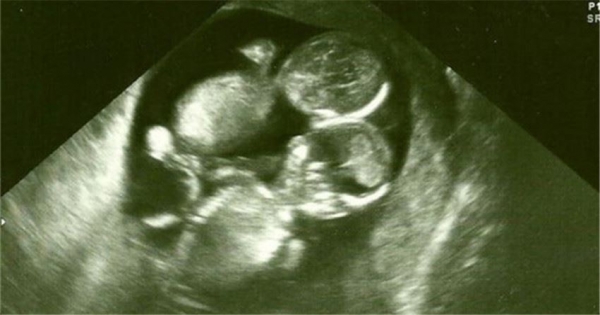

澳洲一名女子「凱特」天生不好受孕,所以和老公兩人領養了兩個孩子,過著溫馨的家庭生活,但是還是一直很希望能擁有自己的孩子的倆人,某天聽到醫生宣布懷上雙胞胎時,簡直不敢相信!然而醫生卻說,凱特的寶寶是罕見的「MoMo寶寶」,也就是「單羊膜雙胞胎」,兩個寶寶一起用一個羊膜,不但容易造成臍帶纏繞而缺氧的狀況,也很容易發展成連體嬰。在這情況下,寶寶的存活率活生生比其他雙胞胎少了一半。因此,醫生建議凱特先不要對外公布懷孕的消息比較好,因為意外隨時都有可能會發生。

凱特就這樣帶著擔憂的心情直到生產當天,醫生替她剖腹取出胎兒之後驚訝發現,這對雙胞胎的確臍帶纏繞,但是卻沒有造成任何負面影響,倆個寶寶依然健康地活著!